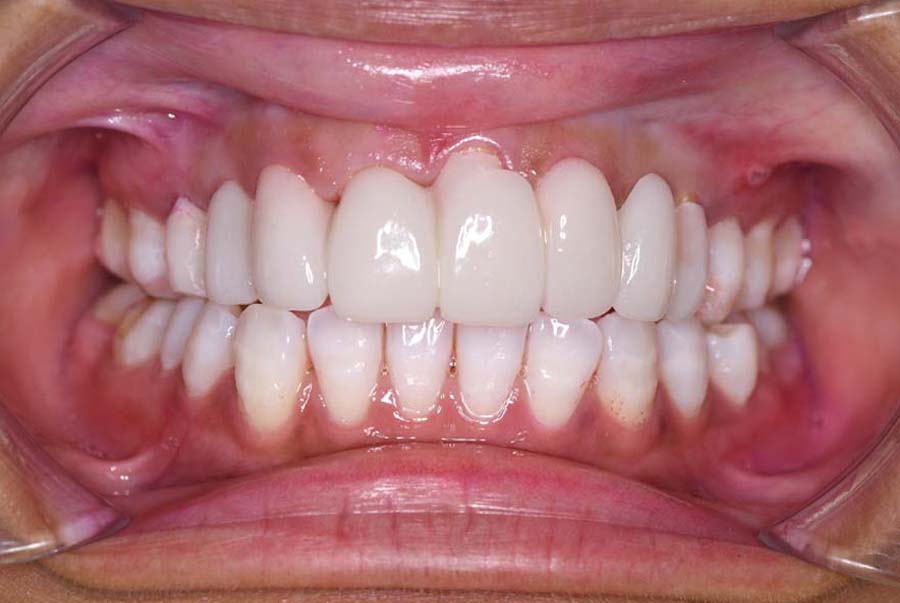

バイトアップ後

| 治療内容 | ①スプリントを装着 ②副子を装着 ③2024年4月 口腔内反映開始 ④副子を入れた状態の所まで咬合を挙上 (バイトアップ) ⑤2024年5月 上顎前歯部8本へ仮歯(TEK) を装着 |